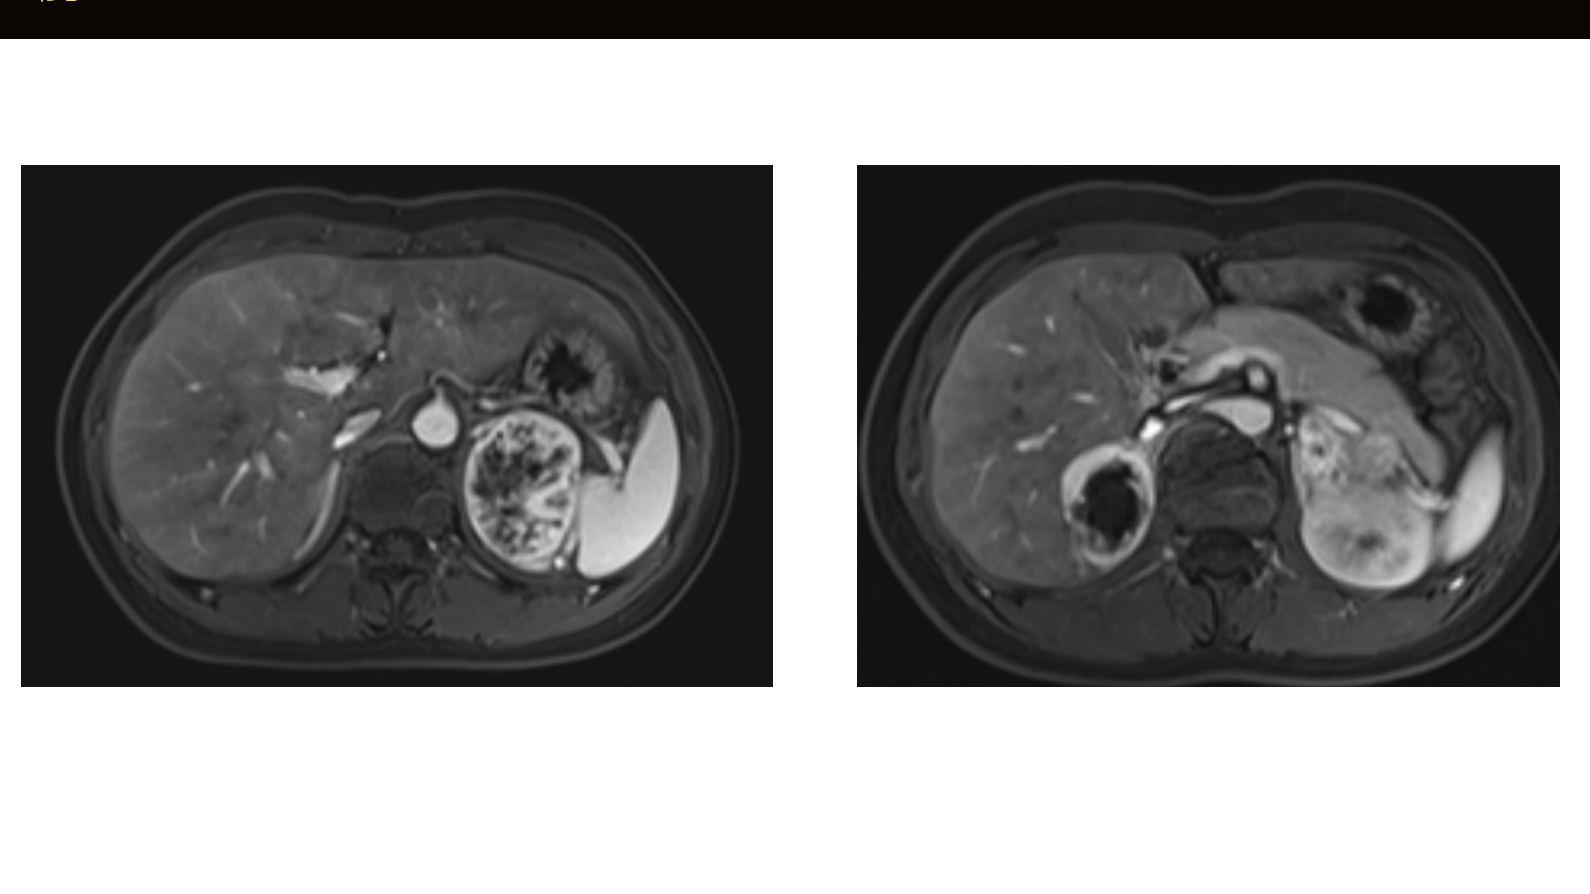

骇人的“高血压”——1例双侧嗜铬细胞瘤的诊治